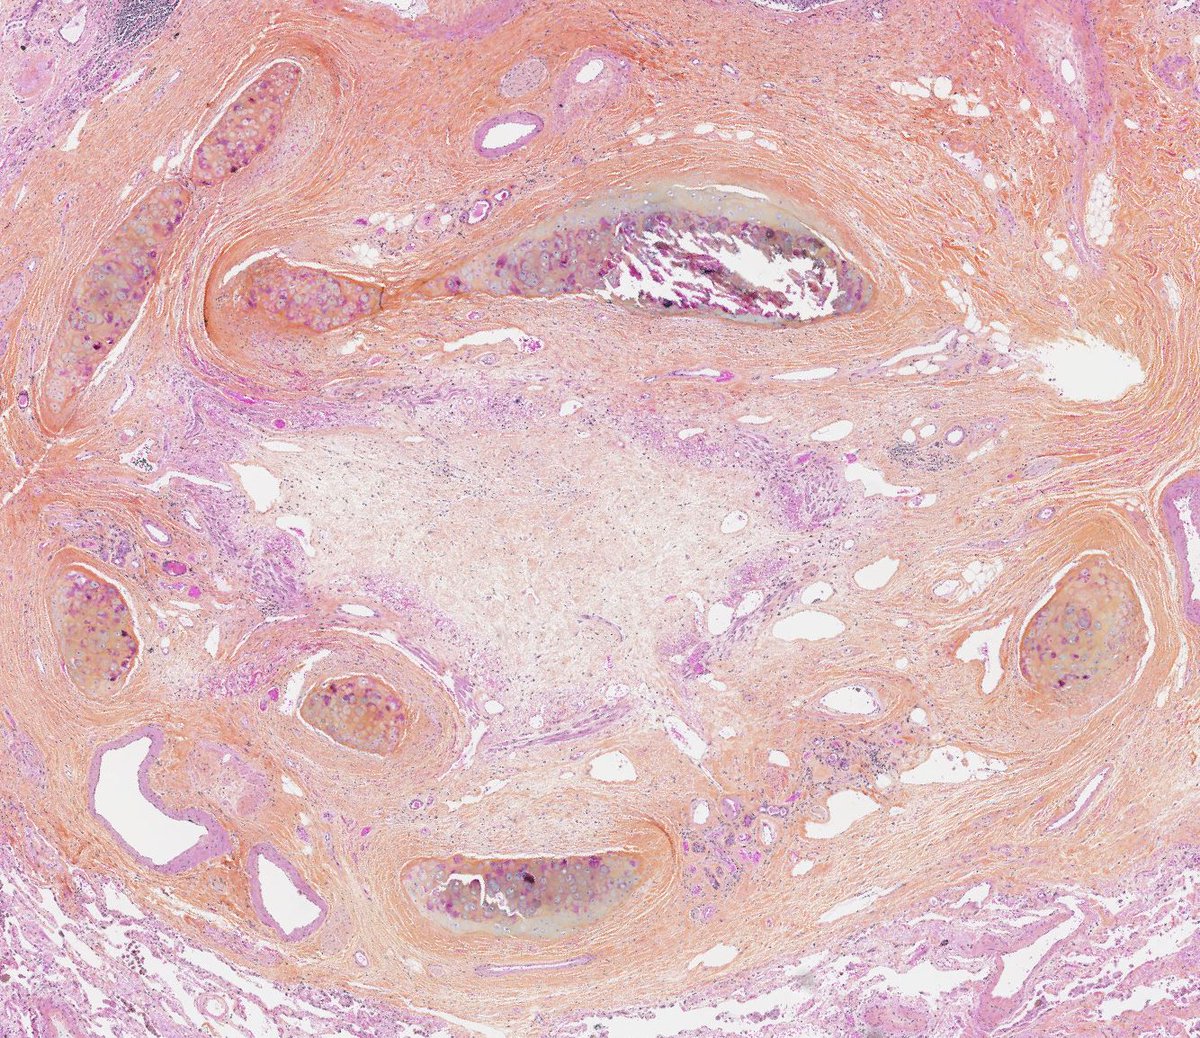

Usual Interstitial Pneumonia shows peripheral, lower predominant fibrosis in the #grosspath by @_Romo_Navarro Microscopically you can appreciate patchy fibrosis, fibroblastic foci & honeycomb #pulmpath #explantsRawesome #transplantpath #ILD